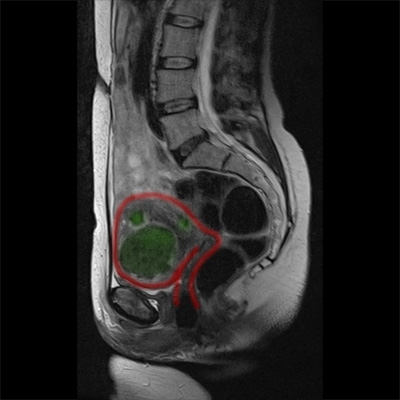

Studium przypadku 47-letniej pacjentki z kilkoma mięśniakami o średnicy do 5 cm.

Obrazy MRT przed leczeniem